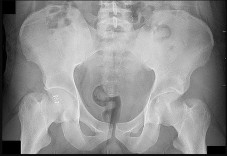

Question 11:

An 18-month-old girl presents with a painless limp and leg length discrepancy. Radiographs show a dislocated left hip with a pseudoacetabulum. What is the most appropriate treatment?

Correct Answer: Open reduction, pelvic osteotomy, and femoral shortening osteotomy

Explanation:

In a walking child over 18 months of age with a completely dislocated hip, open reduction is almost always required. A femoral shortening osteotomy reduces pressure on the cartilage to prevent AVN, and a pelvic osteotomy (e.g., Salter or Pemberton) is usually needed to correct acetabular dysplasia.